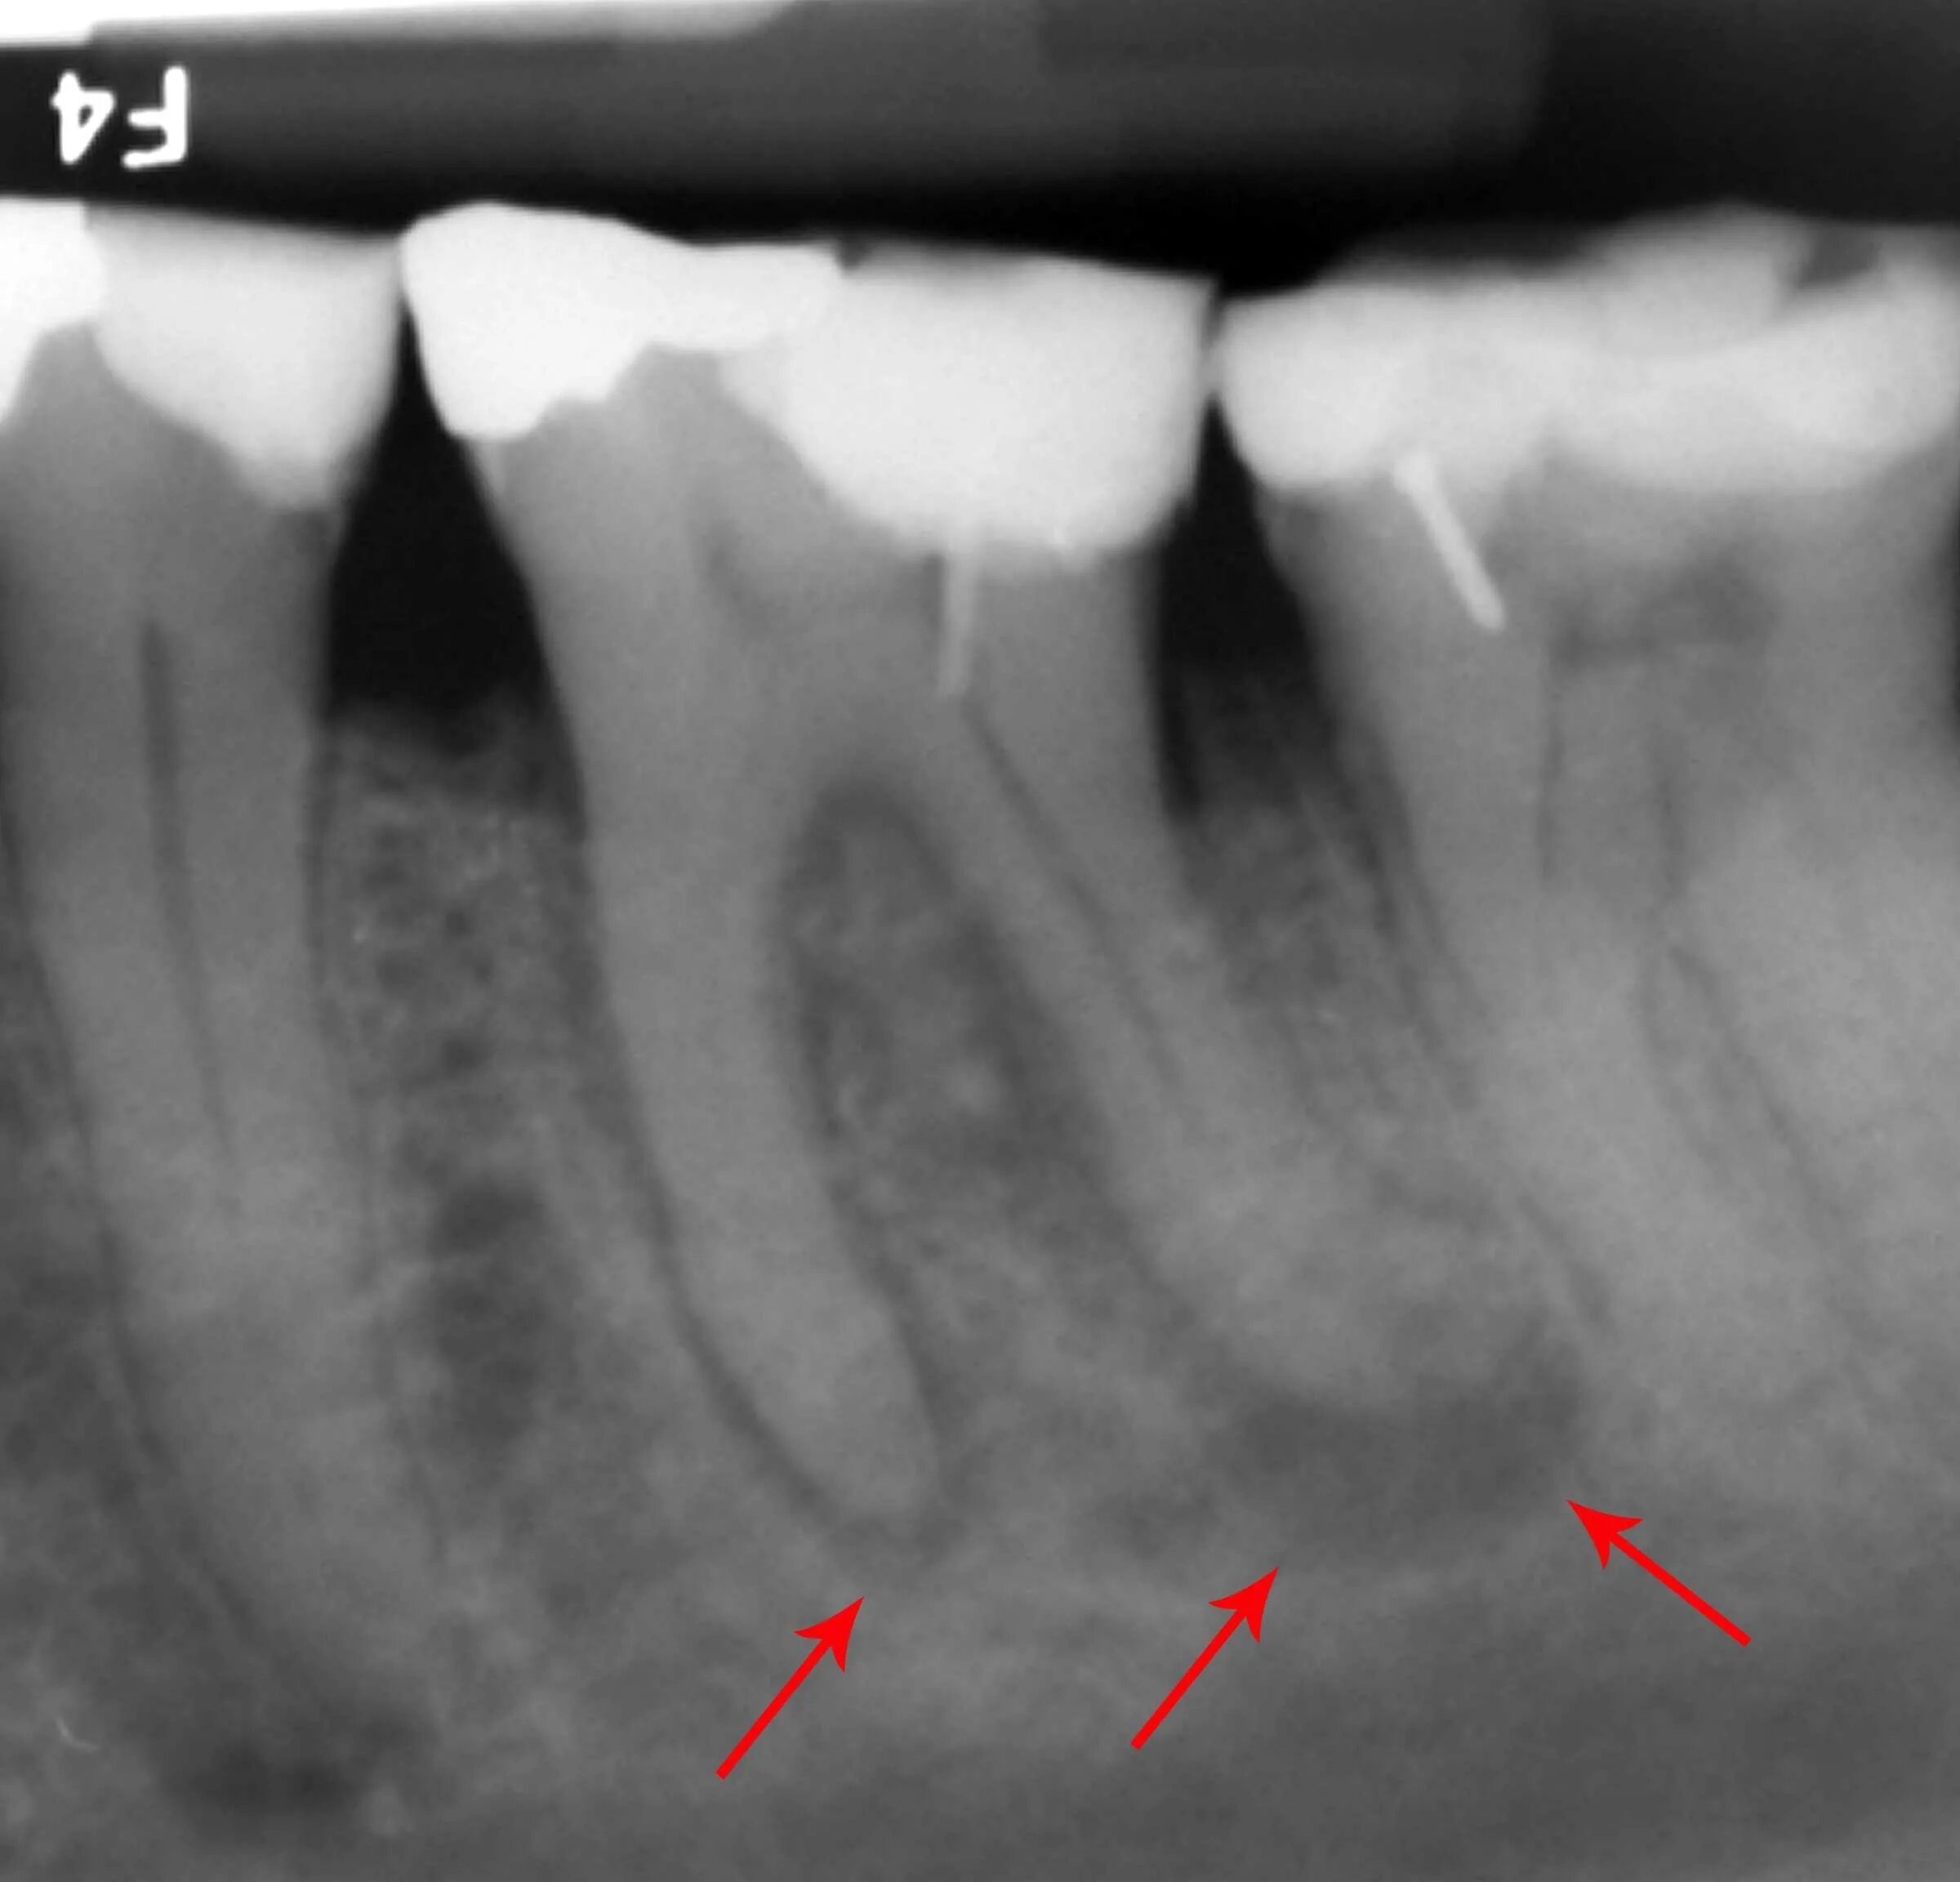

Киста зуба что это